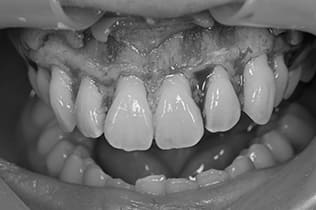

Case01

- 原因

- ガミースマイル

- 治療回数

- 1回

- 治療期間

- 術後治癒も含めて約1か月

- 治療内容

- ガミースマイル改善治療

- 治療費用

- 121,000円

(1ブロックあたり、6前歯部分)

笑った時に歯茎が見えてしまうガミースマイルを改善したいとのことでご来院された患者様です。術後も大変満足していただきました。